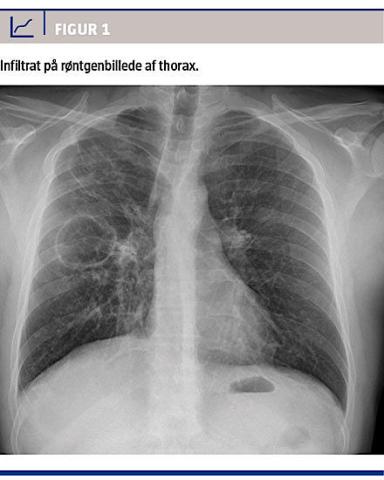

I august 2013 blev en 40-årig russisk mand henvist

til lungemedicinsk udredning pga. hoste, nattesved, feber samt infiltrat på røntgenbilledet af thorax

(Figur 1). Patienten var nogle måneder forinden ankommet som flygtning til Danmark. Han havde i en periode siddet fængslet i hjemlandet. Patienten forklarede, at han i 2011 havde været i behandling for tuberkulose og nu igen følte sig syg. De nærmere forhold ved den tidligere behandling var patienten noget tilbageholdende med på trods af relevant tolk.

Objektivt fremstod patienten som en klassisk tuberkulosepatient: kronisk nedsat almentilstand, feber, vægttab, hoste, bilyde på højre lunge og infiltrat på røntgen af thorax. Paraklinisk sås der let forhøjede infektionstal (C-reaktivt protein-niveau 19 mmol/l og leukocyttal 9,33 × 109/l). Ved mikroskopi af ekspektorat påvistes mange syrefaste stave.